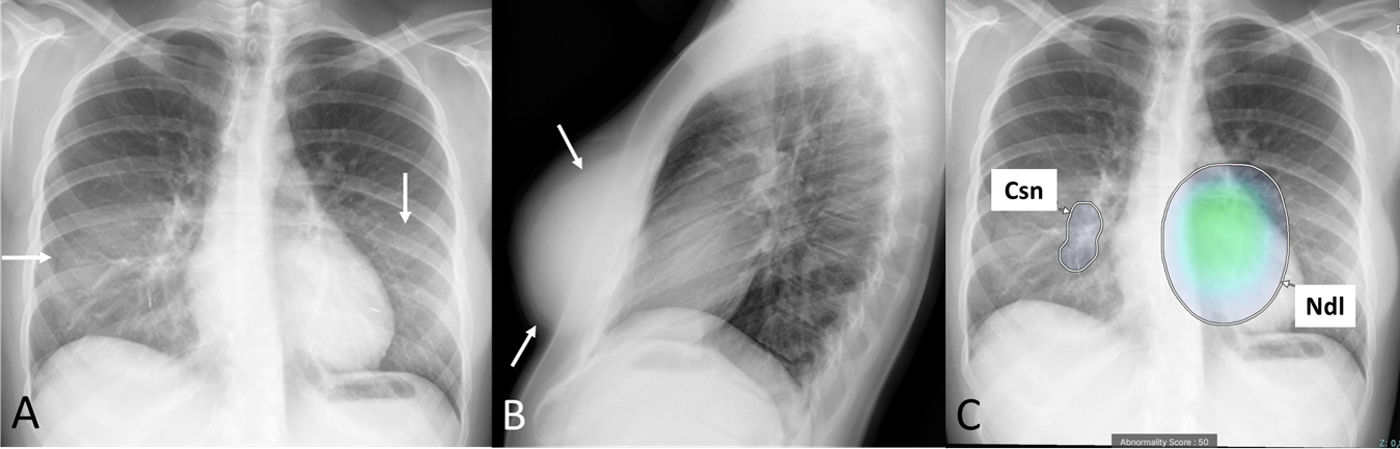

False positive AI results due to breast implants on chest radiographs: The importance of the lateral view

Resultados falsos positivos de la IA debido a prótesis mamarias en la radiografía de tórax: la importancia de la proyección lateral